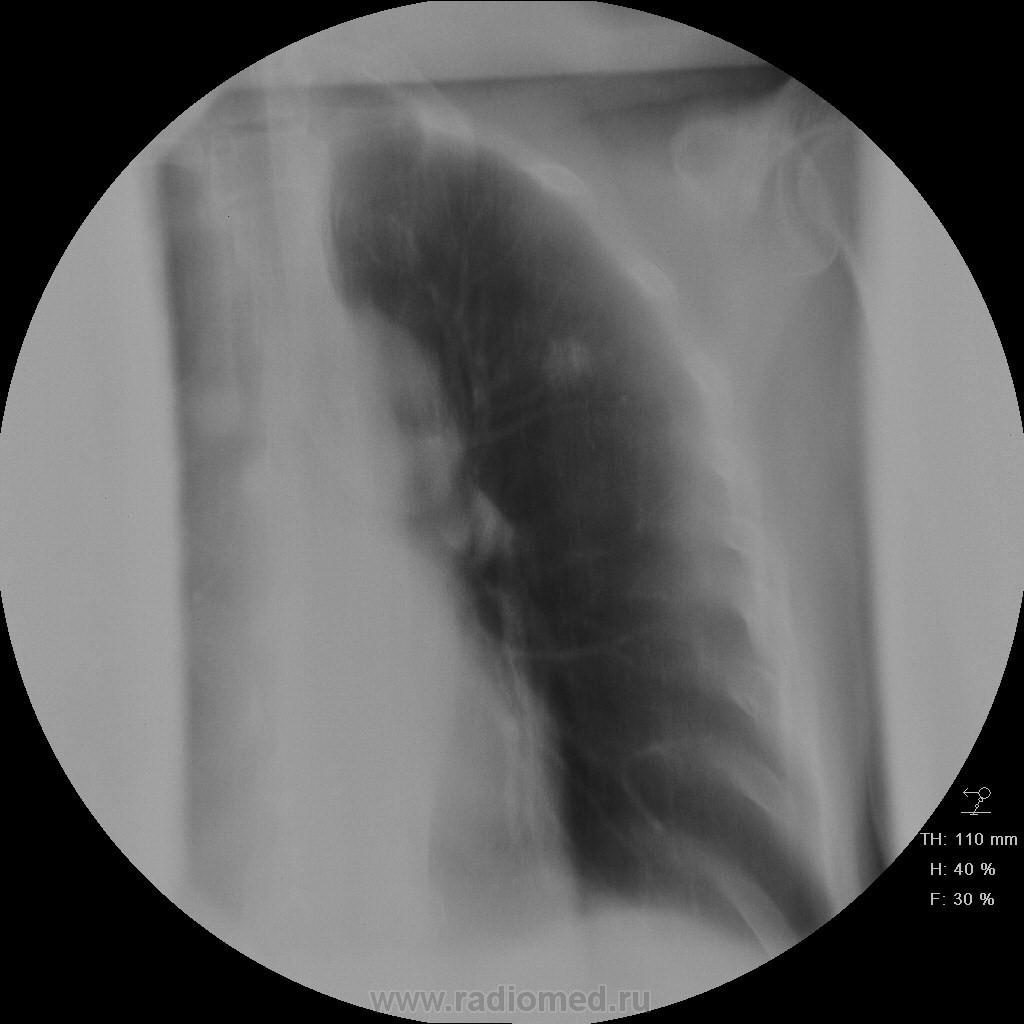

Пациет 60 лет после перенесения ОНМК. жалоб нет ( по легким) . СОЭ, лейкоциты, HB в норме.

Какие будут мнения.

КТ еще не запущен - так что выжимаем все из линейки...

Туберкулез под (?)

У больных с последствиями ОНМК следует думать об аспирационном генезе заболевания. В пользу этого свидетельствует поражение задних сегментов и двусторонняя локализация изменений.